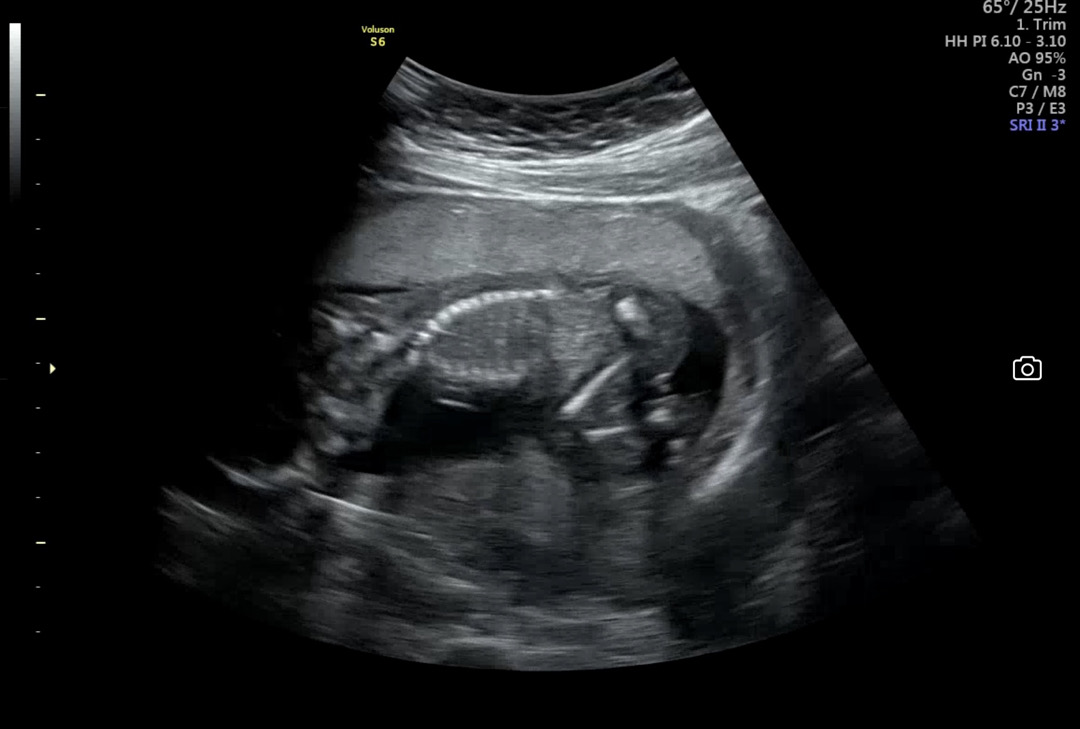

16주 초음파 성별 투표 부탁드립니당ㅜㅜ 의사쌤도 확답을 못 주셨어요ㅠㅠ

제 예상이 맞다면 아들이네요ㅎㅎ 저희 첫째 아들이랑 똑같이 미사일이 보이네요! 엉덩이 쪽에 👇🏻이렇게 튀어 나와있는게 🌶️같습니다!